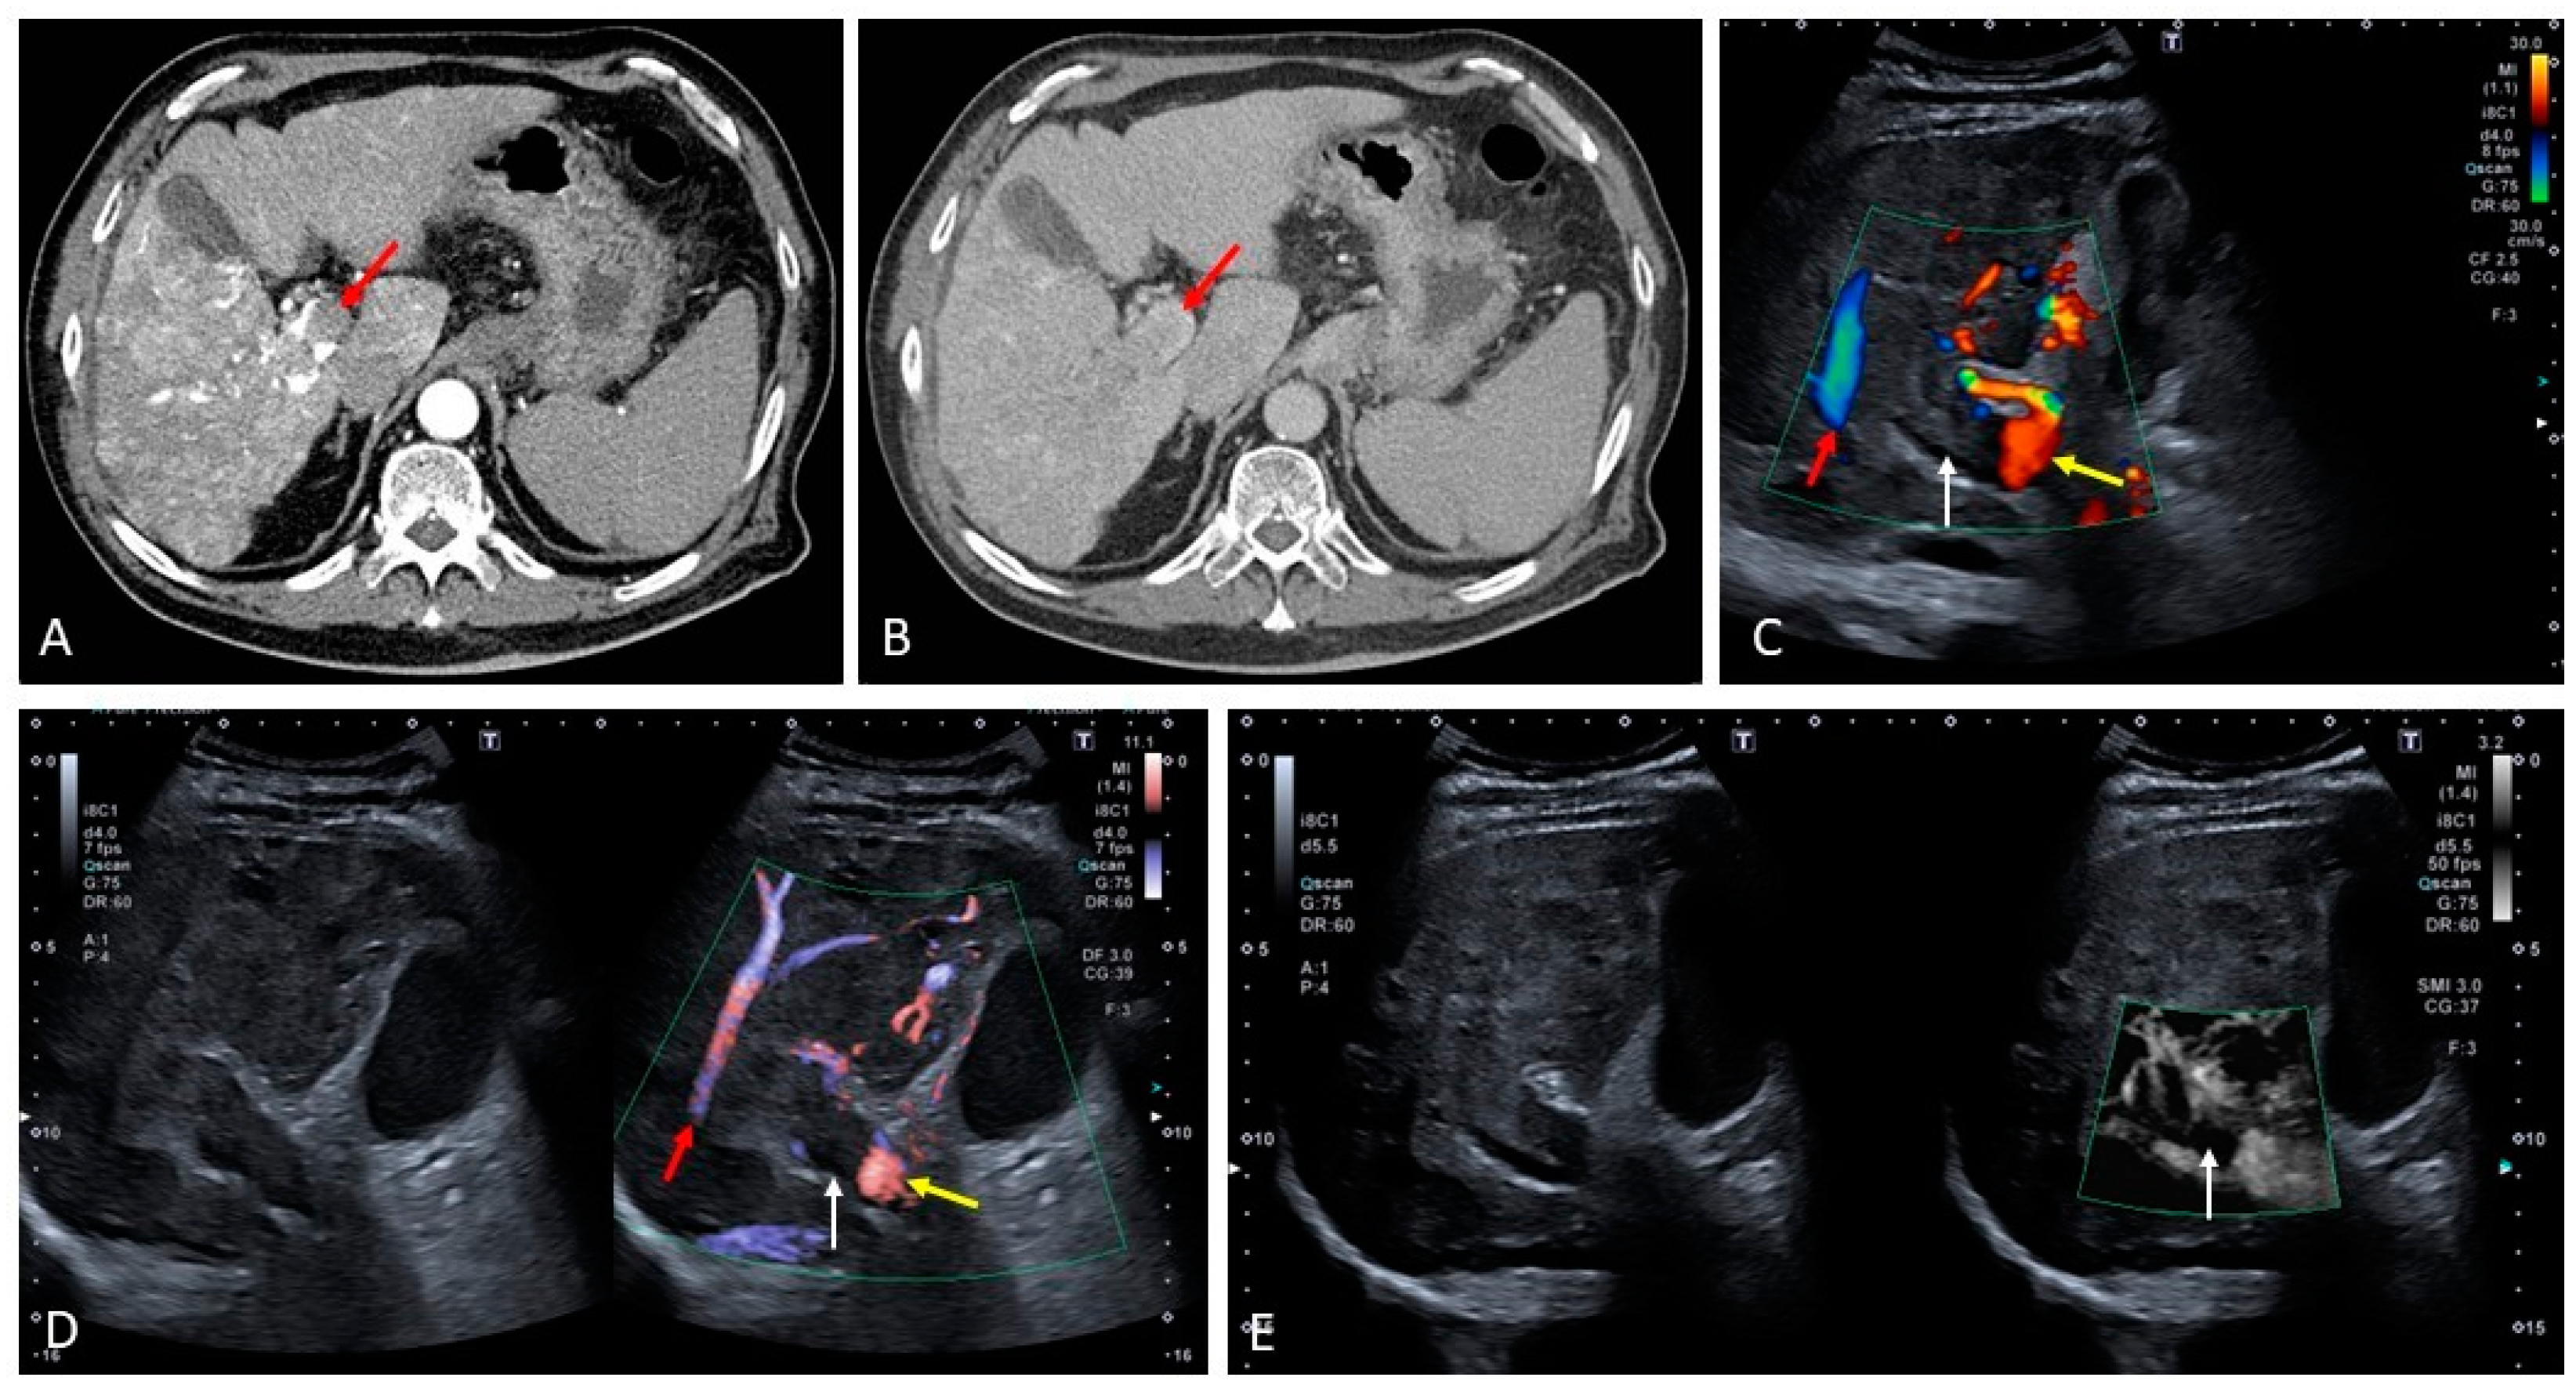

7. Hereditary Hemorrhagic Telangiectasia (Osler–Weber–Rendu Disease)

- Arterio-venous (hepatic artery to hepatic vein)

- Arterio-portal (hepatic artery to portal vein)

- Porto-venous (portal vein to hepatic vein).

- Hepatic artery dilatation > 4 mm.

- Normally, the diameter of the hepatic artery is smaller than that of the splenic artery; thus, an inversion of this relationship may be an early sign of liver VM.

- An increased velocity within the hepatic artery, with a peak flow velocity greater than 100 cm/s.

- Peripheral subcapsular ‘spots’ on power or color Doppler with high arterial blood flow velocities and low resistive indices are suggestive of small peripheral VMs.

- Other ultrasound findings include tortuous intrahepatic tubular structures communicating between the portal venous branches and the hepatic venous branches, tubular structures parallel to the portal branches representing dilated arterial branches, and vascular shunts. Arterio-systemic and arterio-portal shunts have low resistive indices, and arterio-portal shunts may be accompanied by the presence of portosystemic collaterals. Furthermore, arterio-systemic shunts can lead to arterialization, dilation, and turbulent flow of the portal vein and hepatic veins.